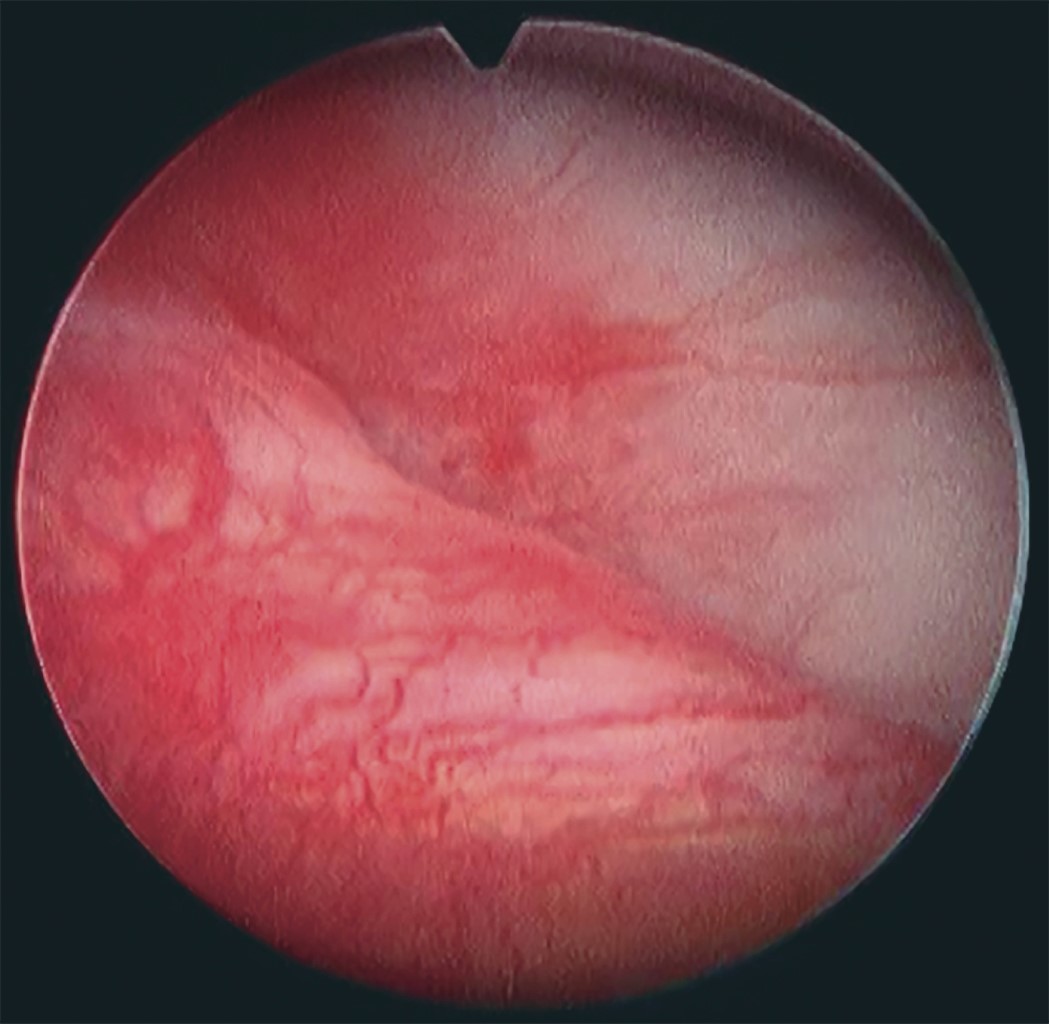

At this point, the diagnosis of the posterior recess is carried out, with the bilaminar zone (Figure 10), the auditory canal afterwards, anteriorly the mandibular condyle, with its transition between the bilaminar zone and the disc, as well as medially the pterygoid shadow.14

Once in the anterior recess, we perform the visual diagnosis, observing the transition line between disc-articular capsule anteriorly (Figure 11), medially the pterygoid shadow.9